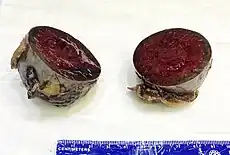

Gross pathology of an accessory spleen